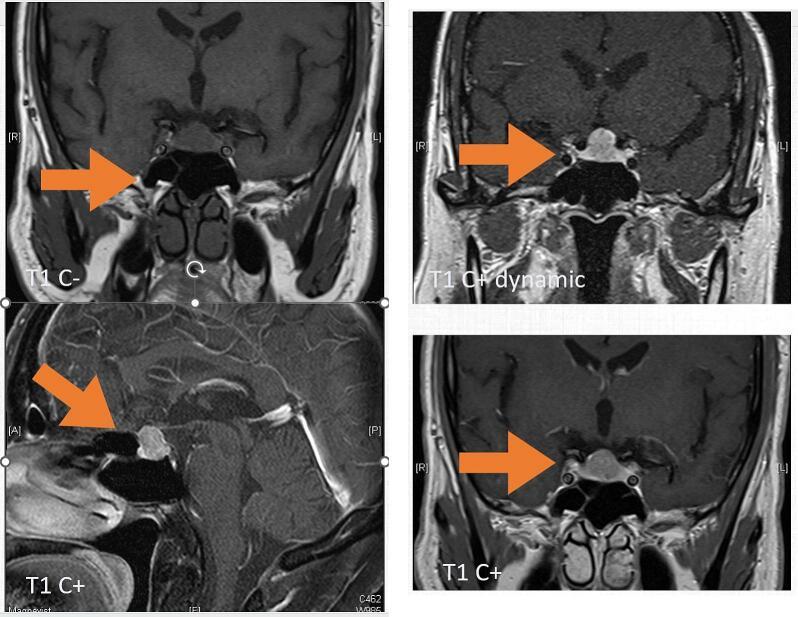

垂体梭形细胞嗜酸细胞瘤:两例报告及文献复习

Pituitary spindle cell oncocytoma: Two cases report and literature review.

Pituitary spindle cell oncocytoma (PSCO) is a seldom-encountered type of pituitary neoplasm with distinctive histological features. It was first described as a distinct entity by Roncaroli et al. in 2002. We present two cases of PSCO and discuss its clinical, radiological, and histopathological features, along with a review of the existing literature.

PRESENTATION OF CASE

Two cases underwent trans-nasal transsphenoidal surgery for tumor resection and had different treatment following would be discussed in this article. Both had unique pathology pattern as Pituitary spindle cell oncocytoma.

垂体梭形细胞嗜酸细胞瘤(PSCO)是一种罕见的垂体肿瘤类型,具有独特的组织学特征。它于2002年被龙卡罗利等人首次描述为一种独特的实体。我们报告两例PSCO病例,并讨论其临床、放射学和组织病理学特征,同时回顾现有文献。

病例介绍

两例患者均接受了经鼻蝶窦手术以切除肿瘤,术后接受了不同的治疗,本文将对此进行讨论。两例均具有垂体梭形细胞嗜酸细胞瘤独特的病理模式。